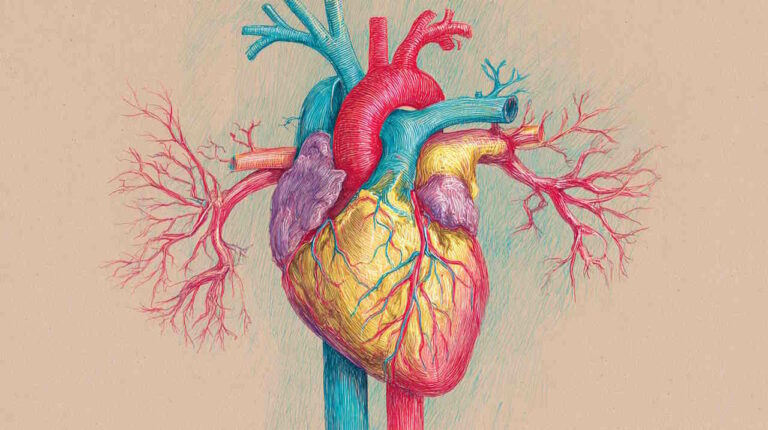

آناتومی قلب

قلب اندامی ماهیچهای است که وسط قفسه سینه قرار دارد. این اندام شبیه مخروطی چهار وجهی است که روی یکی از ضلعهای کناری قرار گرفته است. به همین دلیل قاعده آن سمت دیواره پشتی قفسه سینه و نوک آن سمت دیواره جلویی قفسه سینه قرار دارد. آئورت یکی از سرخرگهای اصلی قلب است که شاخههای آن خون را به تمام بافتها بدن، از سر تا انگشتان پا انتقال میدهند. قلب از پنج سطح (سطح قاعدهای (پشتی)، دیافراگمی (پایینی) و جناغی-دندهای (جلویی) و ششی راست و چپ) و چهار لبه تشکیل شده است.

- لبه راست: این لبه بخش کوچکی از دهلیز راست، بین بزرگسیاهرگ بالایی و پایینی است.

- لبه چپ: این لبه از بطن چپ و بخش کوچکی از دهلیز چپ تشکیل شده است.

- لبه بالایی: این لبه از رگهای بزرگ و دهلیزهای راست و چپ تشکیل شده است.

- لبه پایینی: این لبه از بطن راست و چپ تشکیل شده است.

بخش داخلی قلب به دو حفره بالایی دهلیز و دو حفره پایینی بطن تقسیم میشود. دهلیزها، حفرههای قاعده قلب (بالا) و بطنها حفرههای نوک قلب (پایین) هستند. سپتومها یا تیغههای ماهیچه دو دهلیز (سپتوم بیندهلیزی) و دو بطن (سپتوم بینبطنی) را از هم جدا میکنند. دریچههای قلب بین این حفرهها قرار دارند و جریان خون بین آنها را کنترل میکنند.

آناتومی دریچه های قلب

دریچههای ساختارهای فیبروزی هستند که در هر طرف قلب دهلیز را از بطن و بطن را از ورودی سرخرگها جدا میکنند. دریچه ششی بین سرخرگ ششی و بطن راست، دریچه آئورت بین بطن چپ و سرخرگ آئورت، دریچه سهلختی بین بطن و دهلیز راست و دریچه میترال بین دهلیز و بطن راست قرار دارد.

- دریچههای بین بطنی: دریچه سهلختی از پرده جلویی، سپتومی و پشتی دریچه میترال یا دولختی از دو پرده جلویی و پشتی تشکیل شده است این پردهها بهوسیله حلقه فیبروزی به بافت پوششی قلب متصل میشوند. انتهای آزاد پردهها بهوسیله طناب وتری (تاندونهای بافت پیوندی) به ماهیچههای پاپیلار (۲ ماهیچه بطن چپ و ۳ ماهیچه بطن راست) متصل میشوند. انقباض ماهیچههای پاپیلری در سیتول بطن باز شدن دریچهها را مهار میکند.

- دریچههای سرخرگی: دریچههای هلالی یا سرخرگی از بازگشت خون به قلب جلوگیری میکنند. این دریچهها از سه پرده راست، چپ و پشتی تشکیل میشوند. دو طرف این پردهها به دیواره سرخرگ متصل و بخش بالایی پردهها آزاد است. ضخامت بخش بالایی از سایر بخشها بیشتر است و به آن «لونول» (Lunule) گفته میشود. ضخامت نودول در وسط از سایر بخشها بیشتر است و «نودول» (Nodule) نام دارد.